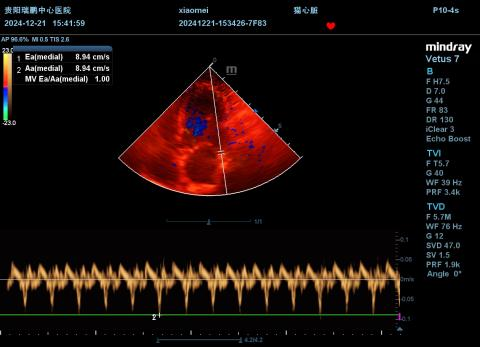

4.4.2 超声心动图(12.21)

图35-45

结果提示:

①舒张末期LVIDd:2.54-2.97cm,EPSS=0.94,左心室较12月15日扩张(LVIDd:2.54-2.97cm,EPSS=0.81);

②舒张末期IVSd=0.38-0.45cm、LVPWd=0.36-0.38cm,室间隔与左室游离壁较上次变薄(IVSd=0.50-0.55cm、LVPWd=0.39-0.55cm);

③FS=8.85-11.36%,左心室收缩功能较上次下降(FS=8.99-15.29%);

④二尖瓣瓣环扩大,轻度反流,反流速度约265.32cm/s,压差约28.16mmHg,反流流速较上次下降(MR Vmax=265.32cm/s),提示左心室收缩功能进一步下降;

⑤LA/AO=1.99,提示左心房扩张;

⑥少量胸腔积液(厚度约0.47cm),较上次明显减少;

⑦综上述,胸腹水减少,考虑与右心衰竭被控制有关,但心脏收缩功能严重受损,因此DCM各项指标均进一步变差。